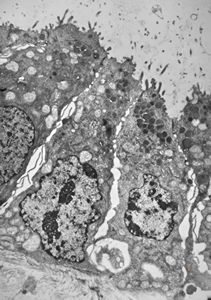

normal mucosa - stomach - parietal cell